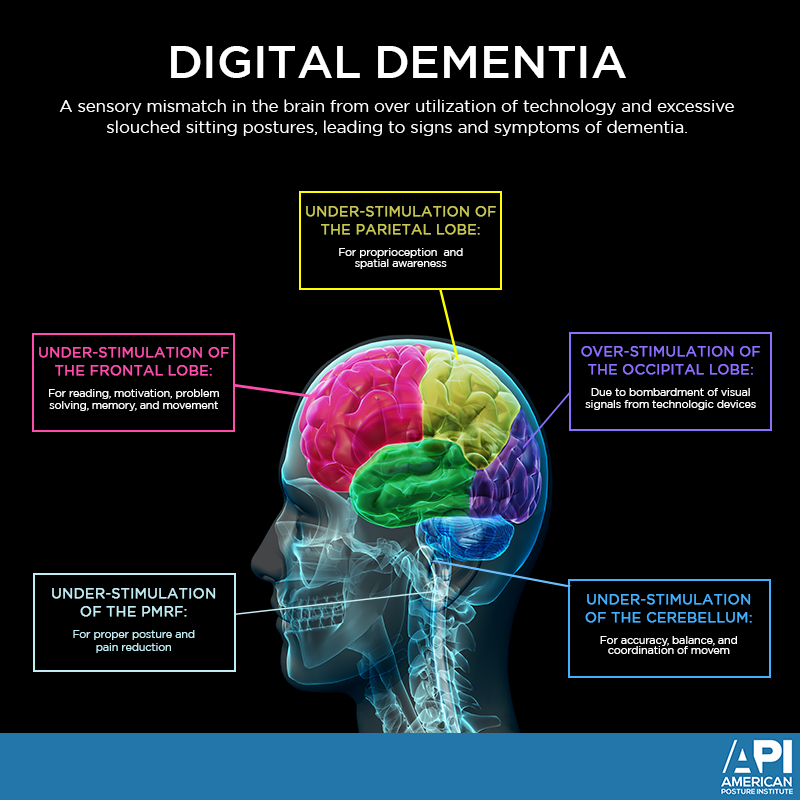

Digital Dementia